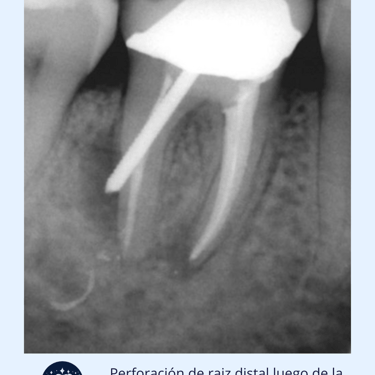

Tratamiento de perforaciones radiculares

Importancia: Las perforaciones radiculares son comunicaciones anormales entre el conducto radicular y el tejido circundante. Tratarlas rápidamente es crucial para evitar infecciones y preservar el diente.

Una perforación radicular puede ocurrir accidentalmente durante un tratamiento de conducto o como resultado de una caries profunda. El tratamiento implica sellar la perforación para evitar la pérdida del diente y prevenir infecciones.

Evaluación Inicial: Examen clínico y radiografías para identificar la perforación y planificar el tratamiento.